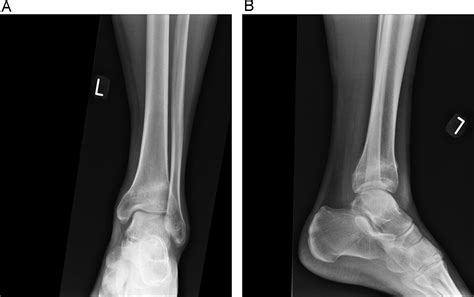

Diagnosis and Clinical Assessment

If you suspect you have a stress fracture, it is vital to seek professional medical advice. A healthcare provider will typically perform a physical examination, assessing the site of tenderness and your range of motion. Because stress fractures are often so small, they do not always appear on standard X-rays, especially in the first few weeks of the injury.

Doctors may suggest more sensitive imaging techniques if clinical symptoms remain high despite a clear X-ray. An MRI is often considered the "gold standard" for diagnosing a stress fracture tibia because it can detect bone marrow edema (swelling inside the bone), which is an early sign of stress-related injury before a fracture line even forms.

• stress fracture tibia x ray

• stress fracture ankle